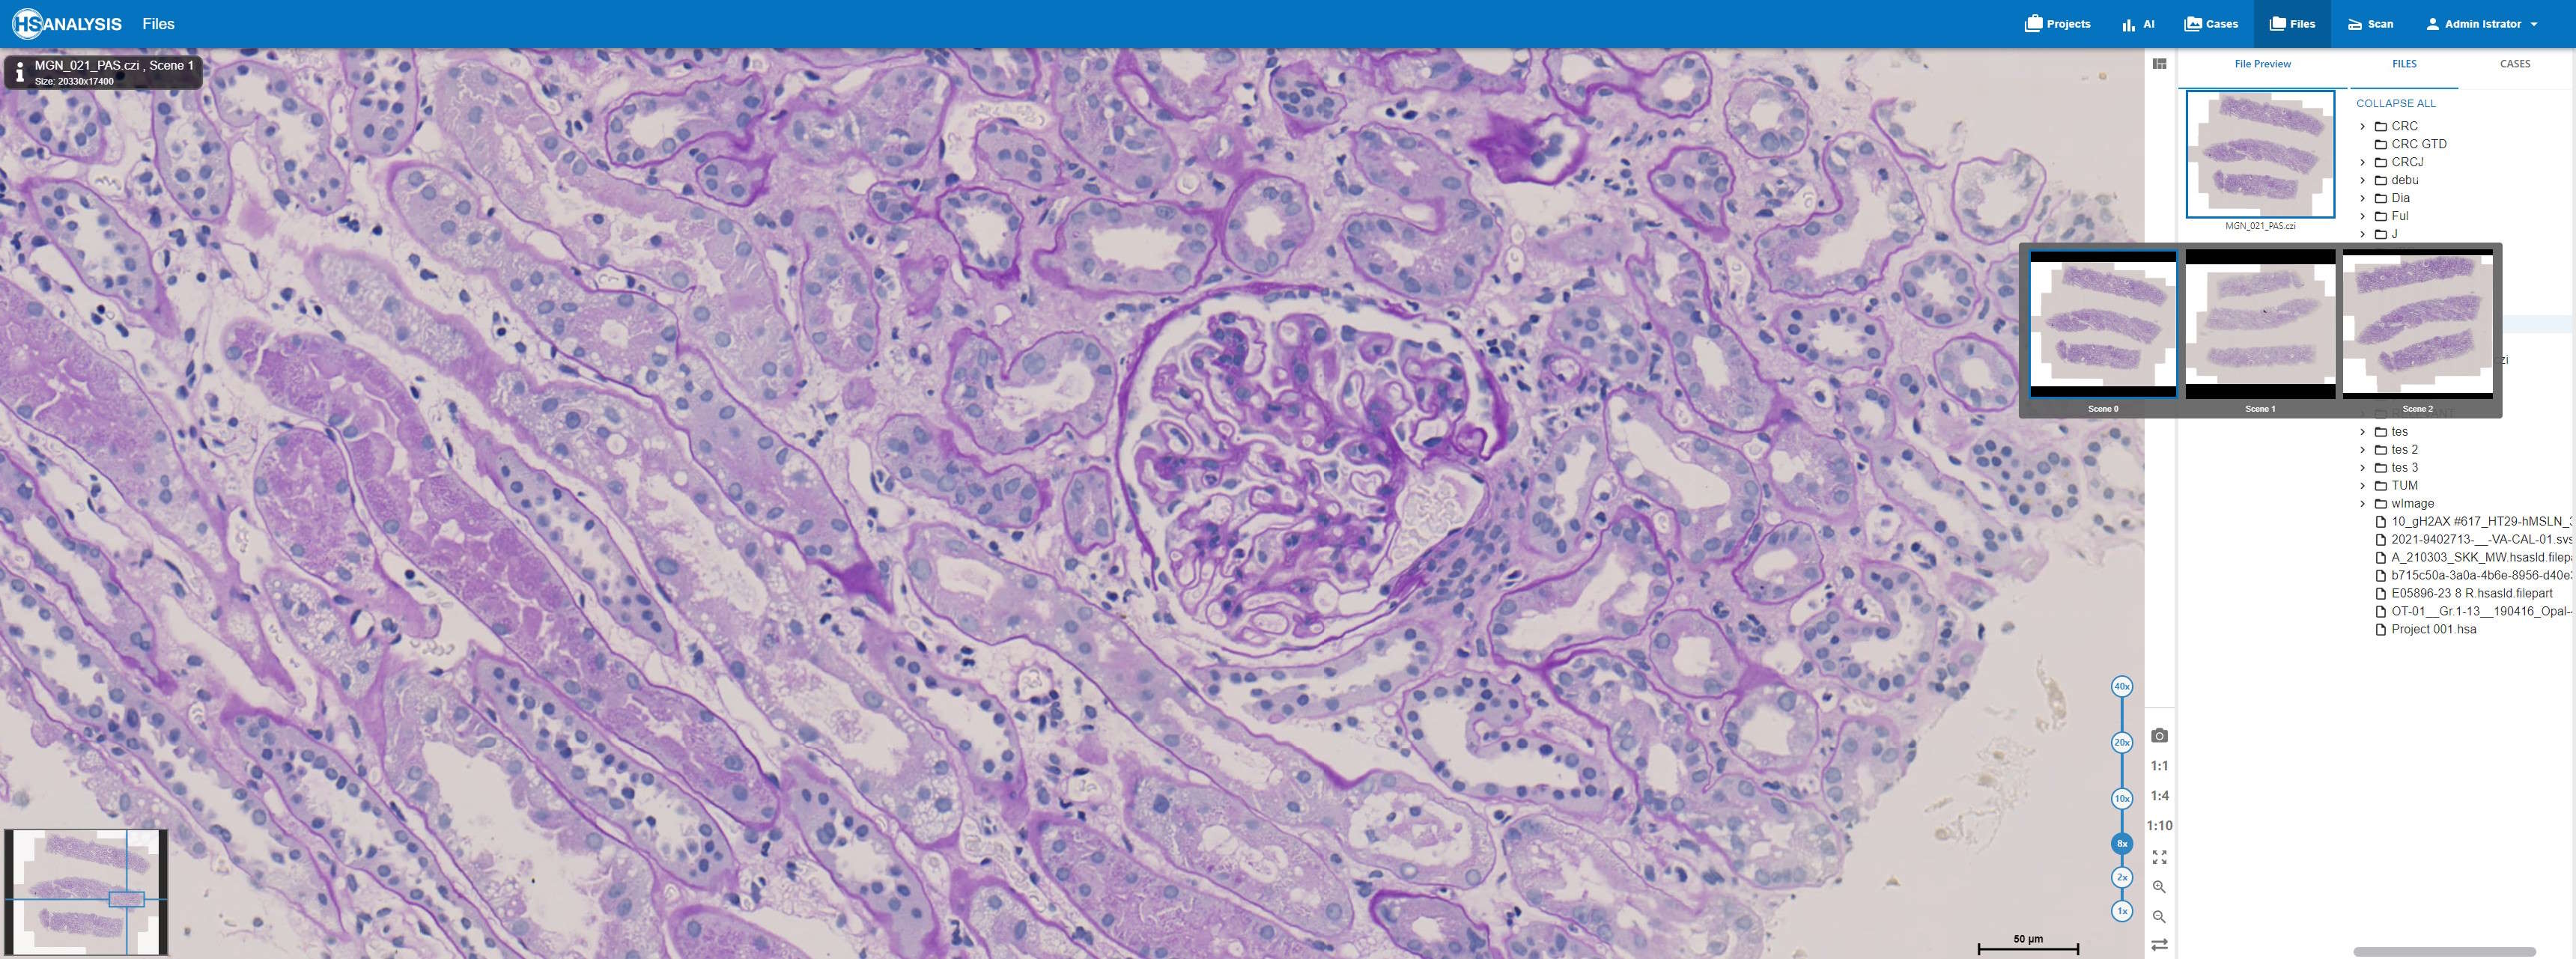

Your Gateway to Seamless Histological Slide Analysis

Are you working with complex histological slides? Do you need a reliable tool to display high-resolution microscopy images in various file formats like CZI, NDPI, SVS, and more? Look no further. HSA Fileviewer is the perfect solution for researchers, pathologists, and medical professionals who need to view and analyze histological slides with ease and precision.

HSA Fileviewer is designed specifically for histology professionals who handle large, intricate microscopy images. We support a wide range of formats, allowing you to focus on your research, not on converting files. With our advanced image rendering technology, you’ll experience unmatched clarity, speed, and control, giving you the power to work efficiently.

2. High-Resolution Image Display

Examine your histological slides in stunning detail with zoom and pan functionalities, allowing for thorough analysis of each region of interest.

4. Intuitive User Interface

With a clean, simple, and user-friendly interface, HSA Fileviewer provides you with the tools you need without overwhelming complexity. Simply the familiar foldetree to navigate through your file and directly see a preview of them.

5. Integrated Scalebar

The scalebar provides an accurate reference for the physical size of the image being viewed. It can be moved around freely, allowing users to measure and verify dimensions of specific areas within the slide for precise analysis.

6. Minimap

The minimap offers a bird’s-eye view of the entire slide, providing a quick overview and allowing easy navigation. Users can instantly jump to different regions of the slide by clicking on the minimap, enhancing workflow efficiency.